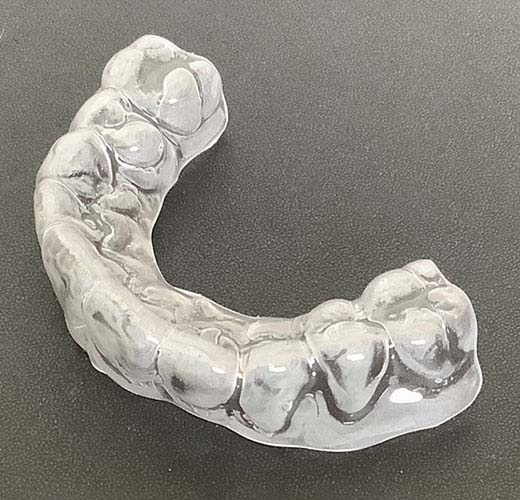

保定期間

矯正治療で歯並びが整った後は、その結果を維持するために保定期間が必要です。

治療後の歯は、最初は不安定なため、安定させるための時間が必要です。

治療が完了したら、リテーナーという保定装置をお渡しします。これにより、きれいに並んだ歯を固定し、安定させます。

お渡しするリテーナー

上顎:取外し可能なマウスピース型リテーナー

下顎:固定されたワイヤー型リテーナー

保定期間中も定期的に通院していただき、経過を観察します。保定装置を怠ると、せっかく整えた歯並びが戻ったり、

悪化したりする可能性があるため、リテーナーの使用をしっかり守っていただくようお願いします。